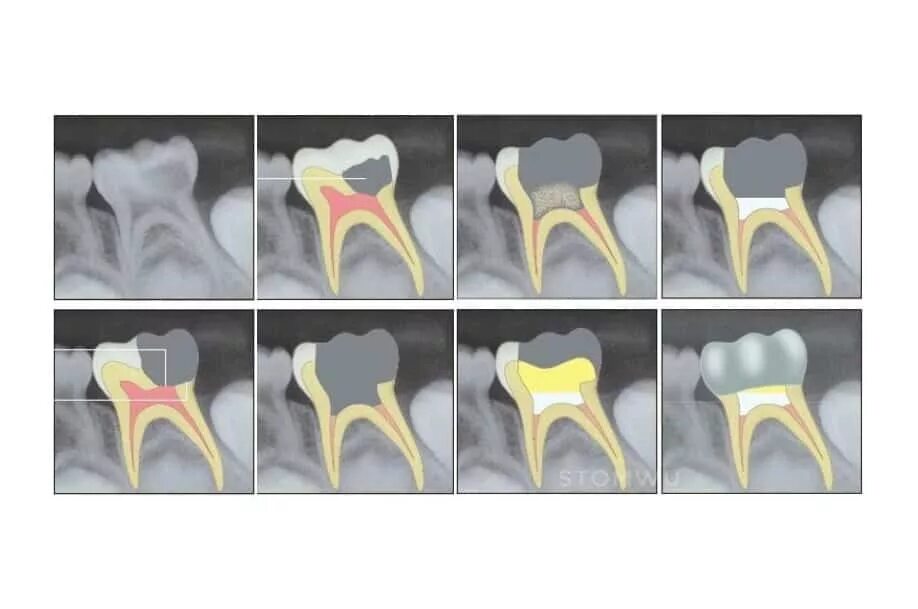

Лечение пульпита с несформированными